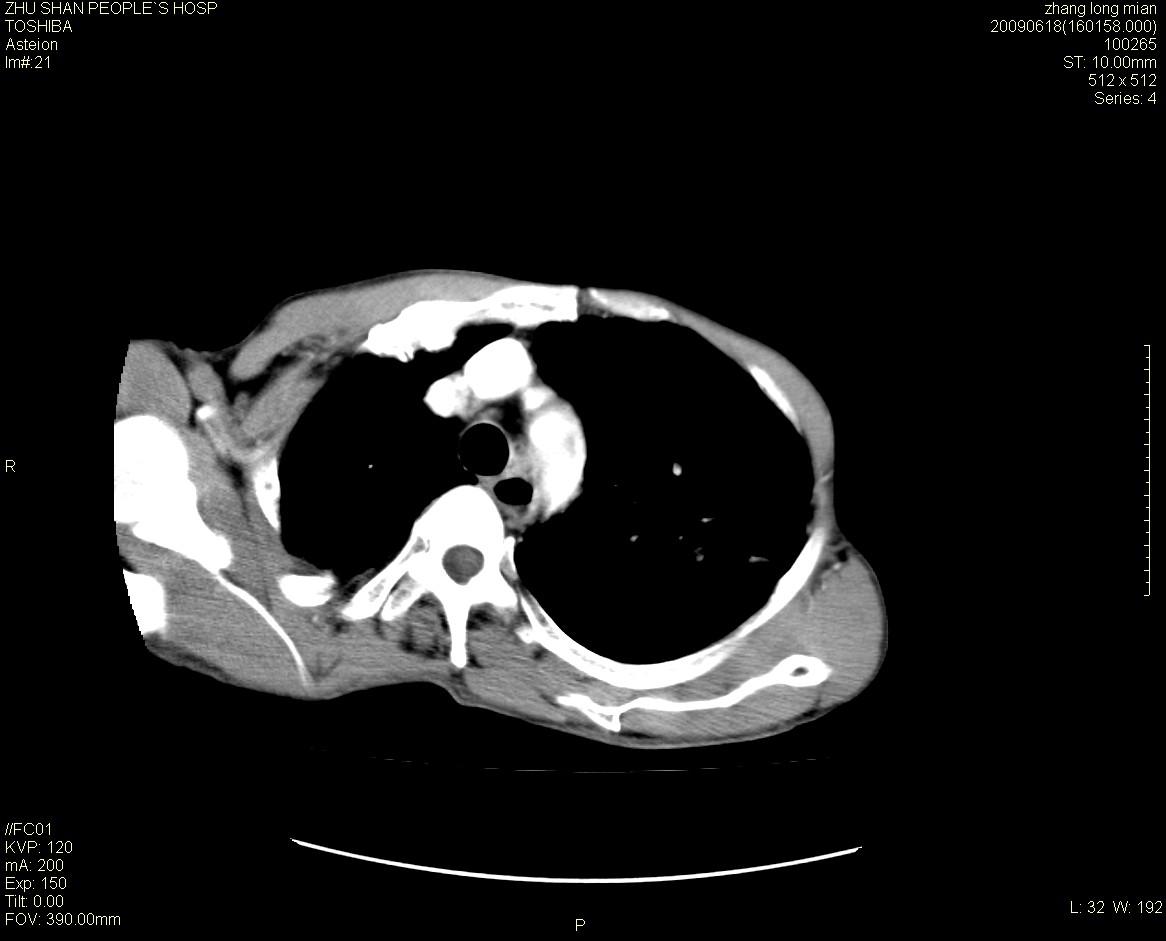

男性 65岁 胸片发现右下肺包块.诊断肺ca并纵隔转移没有问题吧!

两侧胸廓不对称,右侧呈塌陷改变,右肺萎缩。

增强见纵隔区气管隆突上下及左肺门区肿大淋巴结。左肺感染性病灶。

另见右上肺见一枚小结节影,性质待定。